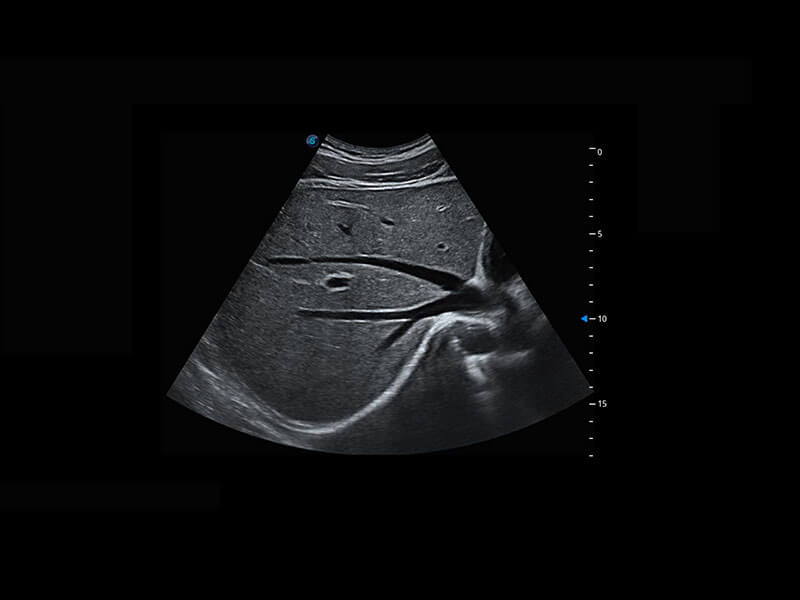

P60提供簡(jiǎn)單易學(xué)易用的高端診斷工具,為您中晚孕篩查提供快速清晰的解剖信息。

S-Fetus能夠助您在實(shí)時(shí)掃查過程中自動(dòng)識(shí)別標(biāo)準(zhǔn)切面、自動(dòng)測(cè)量并錄入報(bào)告。一個(gè)按鍵,即可快速、高效地獲取胎兒生理指標(biāo),簡(jiǎn)化您的產(chǎn)科檢查操作。